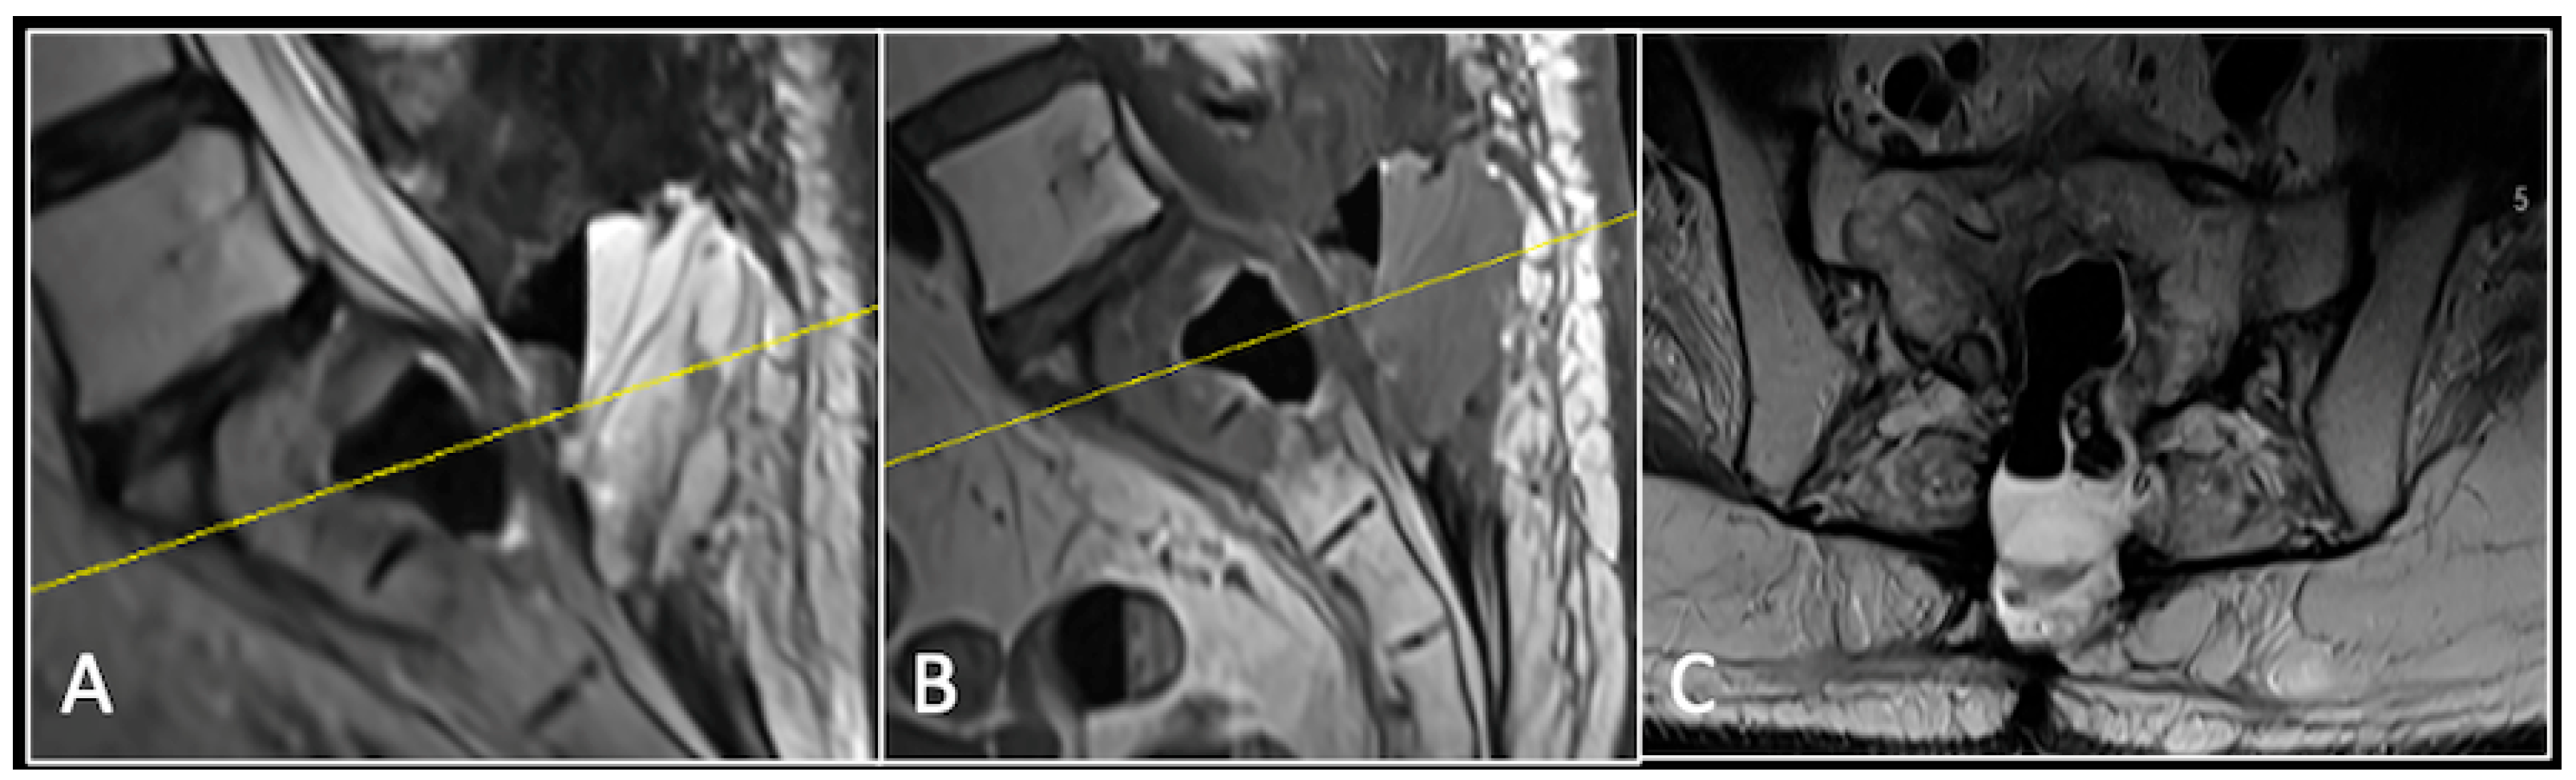

A 73-year-old male presented with an eight-month history of neck pain that was exacerbated on lying flat. He denied any symptoms of myelopathy and radiculopathy. He did not have any constitutional symptoms of malignancy. Past medical history included hypertension, renal cysts, and an ascending thoracic aneurysm. Examination was unremarkable. Diagnostic whole-spine MRI imaging demonstrated a large lobular mass localised to the cervical spine (Figure 2). Biopsy confirmed a conventional chordoma, and he underwent separation surgery followed by adjuvant proton beam therapy. Postoperative surveillance imaging at 12 months demonstrated stable disease (Figure 3).

Figure 2.

MRI demonstrating a destructive lobular lesion localised to the C2 vertebra (chordoma) (arrow). There is significant left-sided extension into the paravertebral tissues laterally and epidural space centrally with indentation of the cord. The yellow line on the sagittal images denotes the level at which the corresponding axial section was obtained. (A) T2-W sagittal; (B) T1W sagittal; (C) T2W axial.